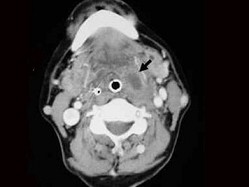

3.女,57歲,頸部不適,CT如圖所示,應診斷為  (    )

正確答案:C

10.CT檢查結果如下,患者的最可能的診斷為  (    )